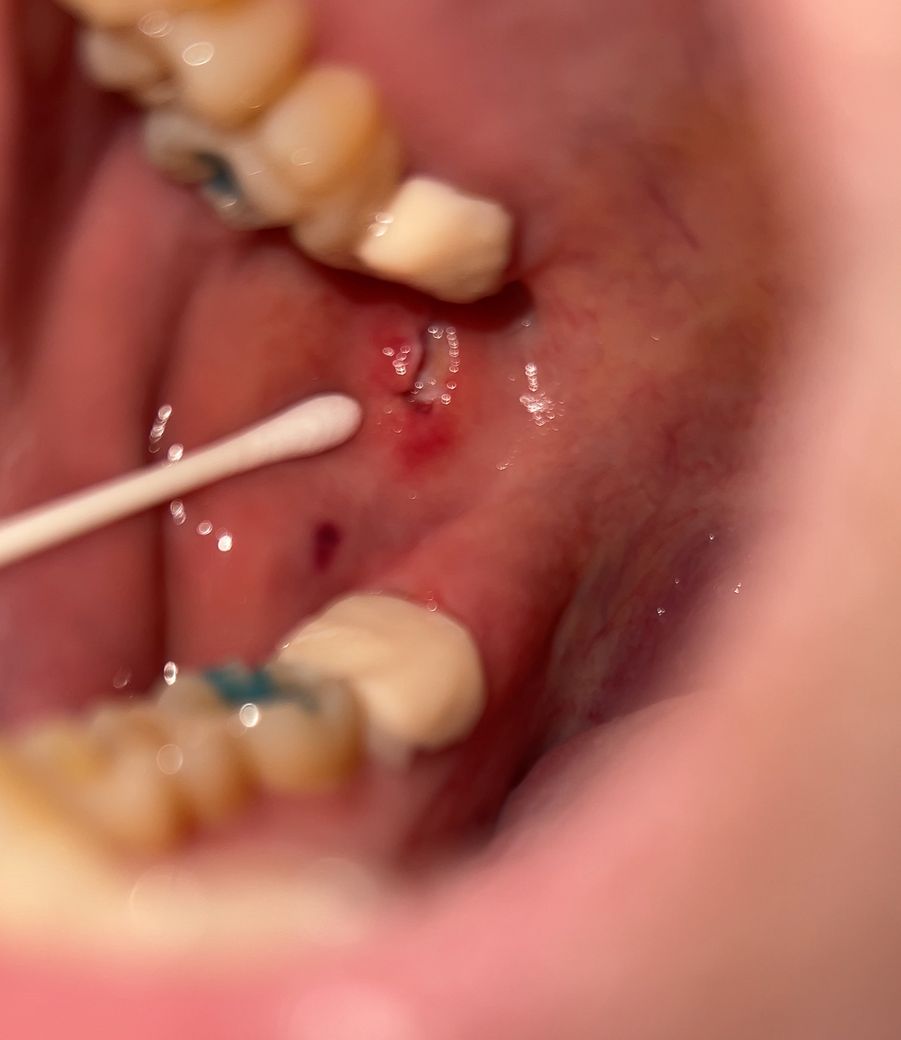

충치치료받은 첫날입니다 임시크라운 씌우기 전 충치 갈 때 볼쪽이 살짝 아팠는데 다하고 나와서 살짝 상처냈다고 하시길래 거울 보니 이렇게 파였는데 꼬메야될정도일까요..? 반대쪽도 크라운 해야되는데 무서워요ㅠ

꼬맬정도의 상처는 아닌것으로 보이며 시간이 지나게 되면 아물게 됩니다. 해당부위 염증이 덧나지 않도록 헥사메딘 가글액으로 가글하여 관리하고 맵고 짜고 신 자극감이 가는 음식은 아물때까지는 피하길 권합니다.

사진이라서 명확한 판단은 어렵지만 꼬매지 않더라도 회복될 겁니다.

잇몸의 회복은 빠른 편이기 때문에 약 2주정도 지나면 눈에 띄게 나을겁니다.

현재 사진 정도로는 꼭 꿰매지 않아도 됩니다. 물론 꿰매면 회복 정도는 빠르겠지만 지금 정도의 회복 패턴이라면 그대로 두면 시간이 지난 이후에 정상적으로 연조직이 회복됩니다. 맨 뒤에 치아를 치료할 때 지금과 같은 상처는 자주 나타납니다.

안녕하세요 치과의사 김철진입니다. 저정도 상처는 통증이 잇긴하긴하겟지만, 시간이 지나면 괜찮아 지실꺼에요. 꼬메지는 않으셔도 될것같습니다.

치아를 삭제하는 도중에 도구로 인해서 올해 연조직에 상처가 많이 생긴 것으로 보입니다 해당 부위를 봉합을 해 준다면 불편감이 더 줄어들고 치유가 빨라질 수 있을 것으로 생각됩니다 자세한 확인을 위해서 치과에서 진료를 받아 보는 것을 권유드립니다